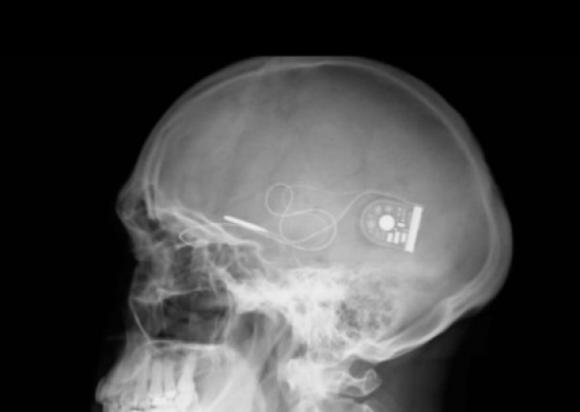

Implantan chip que devuelve parcialmente la vista

El chip se coloca detrás de la retina, desde donde un cable fino llega hasta una unidad de control bajo la piel detrás del oído, permitiendo que los pacientes perciban luz y distingan formas. Por primera vez se ha...